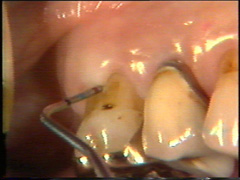

Estas

imagenes fueron producidas por Rolf Attstrom y la Asociación Dental

Dinamarquesa en colaboración con Video Goof, Dinamarca. Cámara y videoediting Tommy Ols, Videocompiling y Grabación

Anders Nattestad